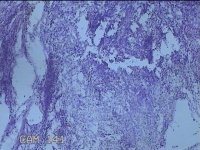

右侧会阴部结节

性别

女

年龄

31岁

临床诊断

皮脂腺囊肿

一般病史

发现右侧会阴部结节2个月。

标本名称

大体所见

灰白暗红色结节1.7x1.3x0.3cm一个,表面糜烂,切开结节呈实性,切面灰白暗红色,质软。

炎症性病变。